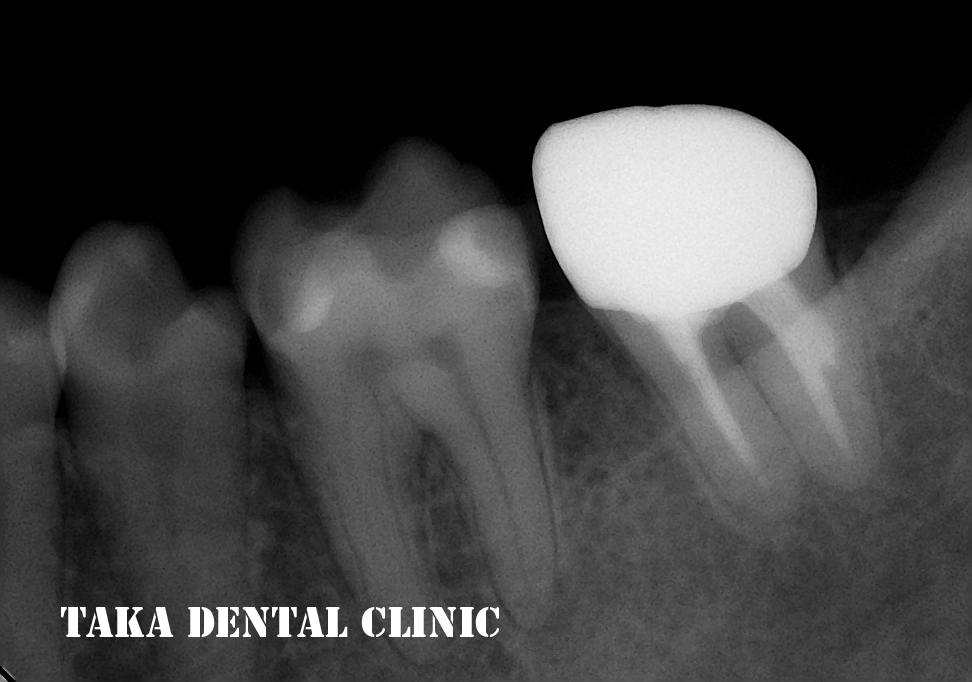

そして、1年後・・・

根の病気もほとんど消失して(根の周りの黒影がなくなっています)、痛みや咬んだ時の違和感も全く無いそうです。